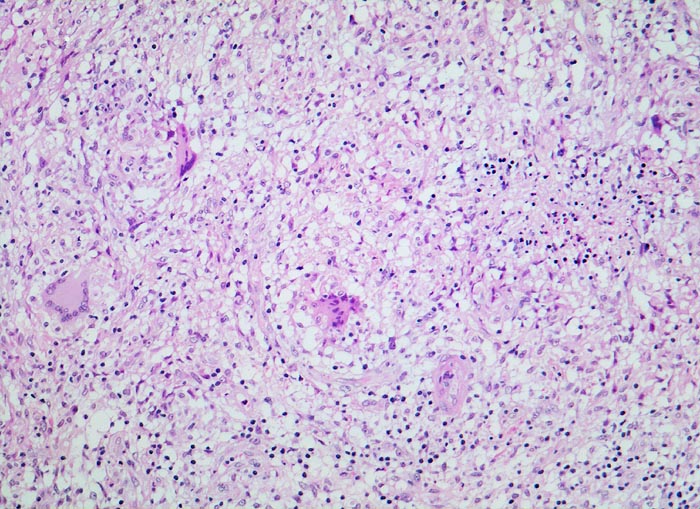

PathoPic – image database / PathoPic ID 3939 - retikulozytär-abszedierende Lymphadenitis bei Katzenkratzkrankheit

retikulozytär-abszedierende Lymphadenitis bei Katzenkratzkrankheit

Lymphknoten, Axilla

Ausschnitt aus der verbreiterten Lymphknotenkapsel mit zahlreichen konfluierten epitheloidzelligen Granulomen mit Riesenzellen. Auf diesem Bild ist lediglich eine kleine umschriebene von Granulozyten durchsetzte Nekrose sichtbar. Die Riesenzellen sind teils vom Fremdkörpertyp mit unregelmässig angeordneten Kernen, teils vom Langhans Typ mit hufeisenförmig in der Zellperipherie aufgereihten Kernen.

Druckschmerzhafte Lymphknotenvergrösserung in der rechten Axilla 2 Wochen nachdem der Patient von seiner Katze an der rechten Hand gekratzt wurde.